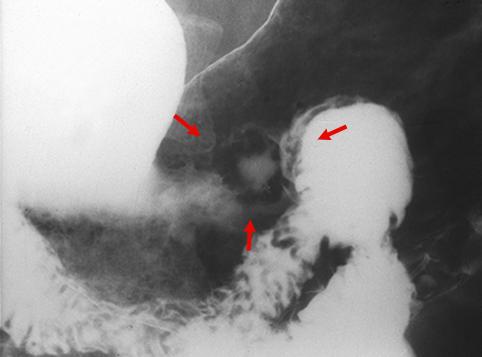

Cáncer Precoz del Estómago, tipo IIa+IIc, crecido en el tercio inferior

Tumor Epitelial Maligno/Adenocarcinoma

estómago(región)/cuerpo

Rayos X

Tipo 0(tipo superficial)/Tipo IIa(IIa+IIc)

15 - 19

sm